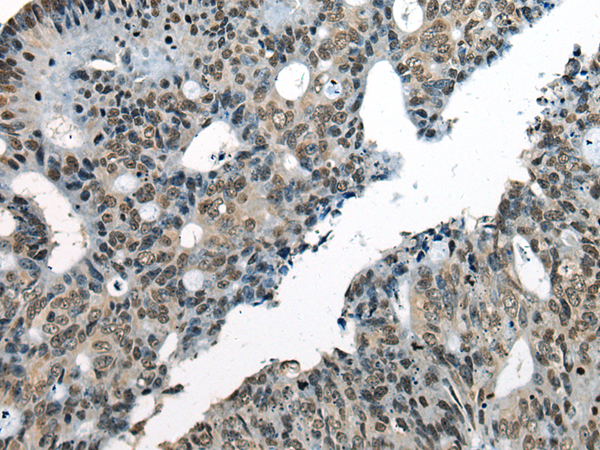

This gene encodes a DNA helicase protein involved in DNA repair. The protein converts ATP to add poly(ADP-ribose) as it regulates chromatin relaxation following DNA damage. Several alternatively spliced transcripts variants have been described for this gene. |

ELISA, IHC |

CHD1L |

chromodomain helicase DNA binding protein 1 like |

IHC positive control: |

Human colorectal cancer |

IHC Recommend dilution: |

25-100 |